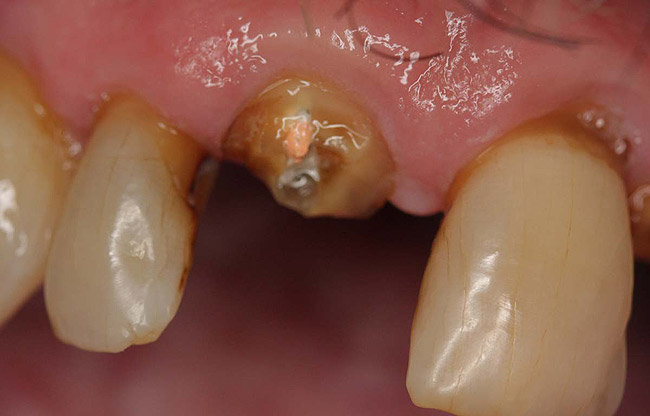

Figure 16  The fractured central incisor root.

Figure 16